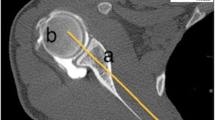

Although geometrical considerations of these studies seem valid, measurements were conducted based on 3D-CT models of the entire torso, which is neither practical nor feasible due to radiation exposure. In a clinical setting surgeons rely on plain-radiographic imaging, clinical examination and possibly CT scans or MRI of the affected shoulder. For the determination of SIR, two obstacles need to be faced: First, the field of view (FOV) is often limited, and the spine not sufficiently depicted in the CT/MRI-scans, and therefore body axes cannot easily be determined. Furthermore, obtained values for scapulothoracic orientation might be affected by the supine position, as pressure to the medial ridge of the scapula might decrease internal rotation and protraction of the shoulder. Secondly, SIR is defined by the relation of the scapular axis (line from the trigonum scapulae to the center of the glenoid) to the transversal body axis. (Fig. 2) While clinically the trigonum scapulae can be accessed non-invasively through palpation, the center of the glenoid cannot be determined. Therefore, apical landmarks like the acromion, the coracoid process tip or the acromioclavicular (AC) joint are used to determine scapulothoracic orientation [6, 8,9,10,11,12]. Considering, that with increasing thoracic kyphosis the scapula shifts anteriorly, subsequent anterior tilt around the scapular axis is seen which could possibly alter the measured SIR based on apical landmarks.

A Measurement of scapular internal rotation (SIR) in a 3D model in respect to the sagittal body axis. B Anterior scapular tilt was measured on an “en face” view of the glenoid in respect to the examination table as a reference of the coronar body axis. C 2D measurement of SIR in respect to the standardized transversal reference line with a limited field of view

Measurement of scapula orientation

Whole-body CT scans were exported, anonymized, and rendered into 3D models using Horos software (Horosproject.org; Nimble Co LLC d/b/a Purview in Annapolis, MD USA). As previously described [7], SIR was defined as an angle between a perpendicular line to the best-fit sagittal axis (midpoint from the vertebra body Th1 and midpoint of the sternum) and a line from the medial root of the scapular spine (trigonum scapulae) to the center of the glenoid (Fig. 2A). Anterior scapular tilt was defined as an angle between the midpoint of the glenoid and the inferior angulus and a line drawn vertically along the fixed examination table (Fig. 2B) on a parasagittal view in a 3D model. For independent determination of 2D scapular internal rotation, whole-body CT scans were cropped on an axial view leaving only the scapula and humerus from the acromion to the level of the inferior angulus and excluding visualization of the spine, comparable to a standard clinical CT scan field of view. Internal scapular rotation was then measured at the level of the deepest glenoid concavity as the angle between the midpoint of the glenoid to the medial root of the scapular spine and the standardized CT reference line for the transversal axis. (Fig. 2C).